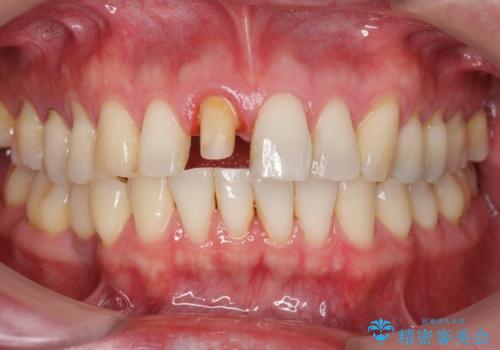

前歯の変色を改善!セラミック治療

- 前歯の変色が気になり審美障害の改善を求めて来院されました。

根管治療に伴う歯の色調変化はよく見られる所見です。

セラミッククラウン製作を行い審美性の改善を計画します。